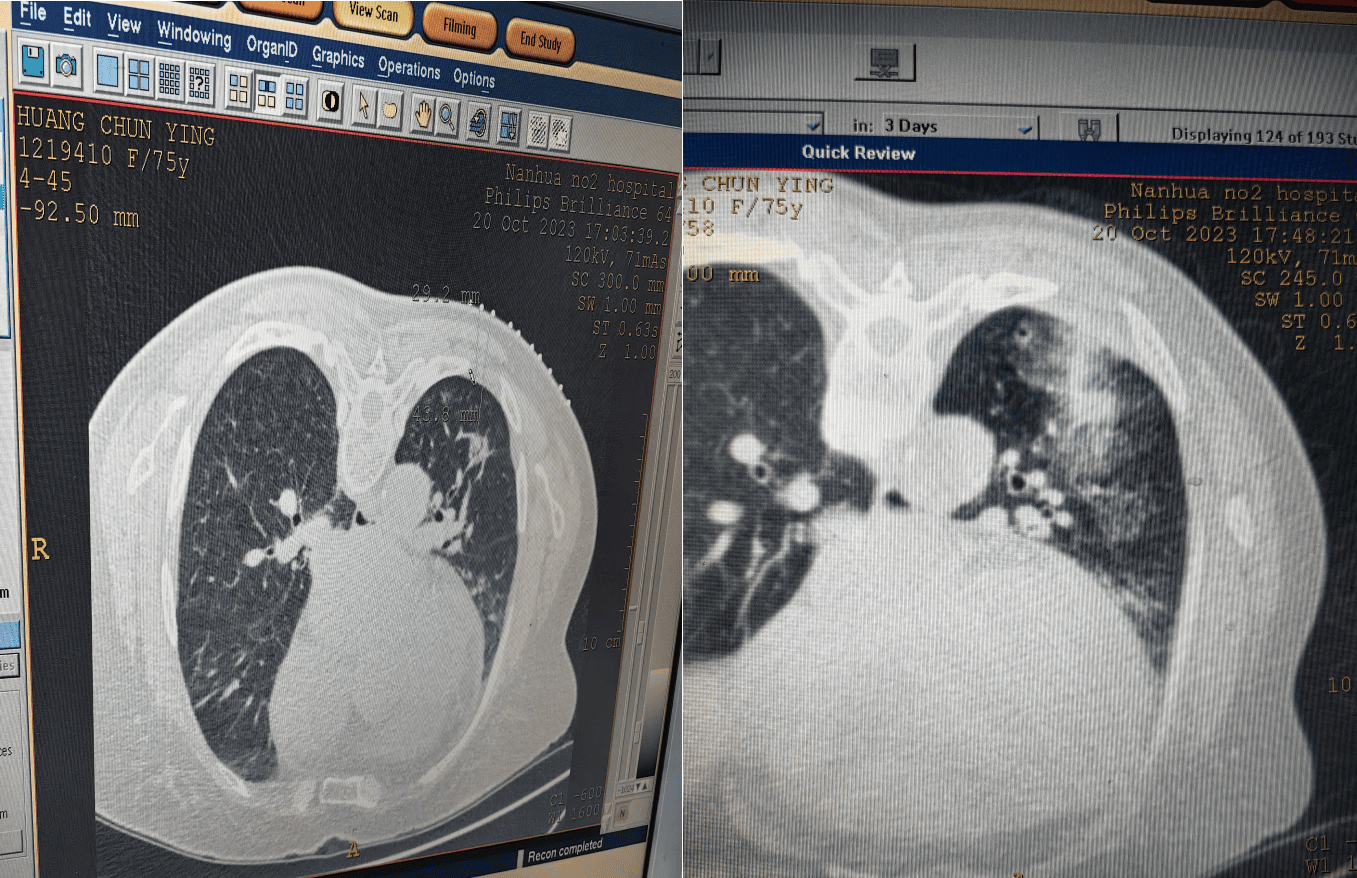

病友黄女士,75岁,因“双肺多发结节:肺癌可能性大”就诊于我院呼吸与危重症医学科,术前谭小武教授团队经过综合论证评估,以诊疗规范化、标准化、微创化和病友诊疗获益最大化原则为黄女士制定了微创介入手术方案。

在介入中心医护团队密切配合,在呼吸与危重症医学科主任谭小武带领指导下,吴旭博士在手术助手的配合下沉稳娴熟地操控着穿刺针、调整消融参数等消融机器系统进行精准的穿刺定位、消融,不到20分钟即顺利完成消融术。黄女士全程未感疼痛、呼吸困难和其他不适。即刻复查胸部CT显示消融后呈现规整“圆中圆”晕完整包绕了结节,未见出血及气胸并发症。